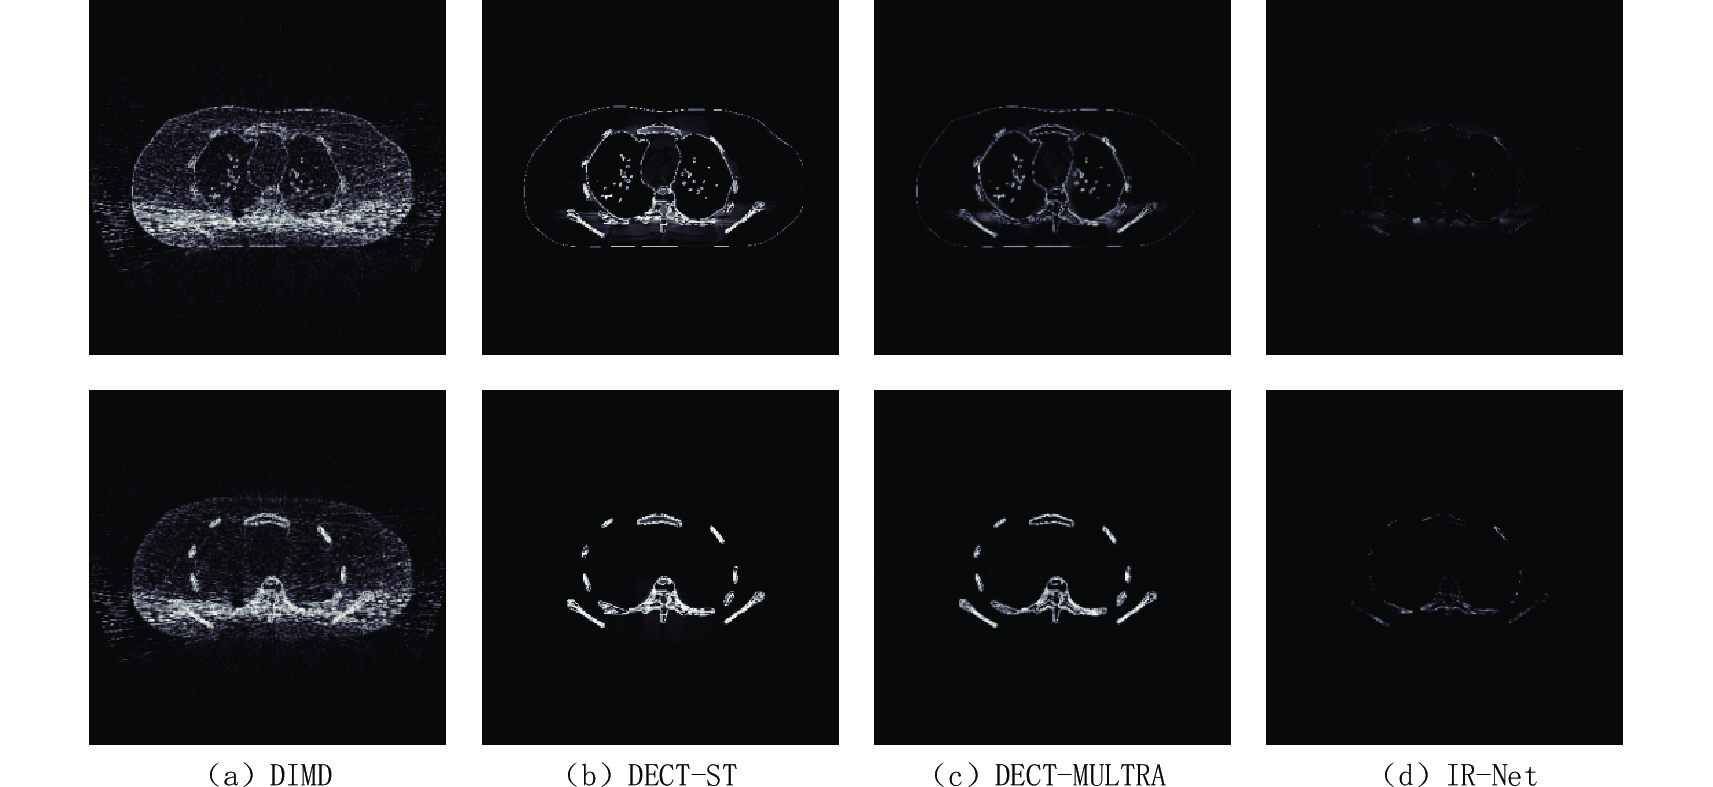

为了进一步评价所提方法的优点,图4显示了分解结果偏差的绝对值,提供了视觉上的噪声抑制性能比较,每种基材料的显示窗口为[0 0.3] g/cm-3。通过对比可知,本文方法对分解结果的偏差最小。总的来说,IR-Net网络避免了繁琐的参数调节,提高了材料分解精度,保持了图像边缘清晰。

为了定量评价IR-Net网络在材料分解中的性能,分别计算每种方法下基图像的RMSE、PSNR和SSIM,其结果如表1。由表1知,DIMD获得的两种基材料图像的RMSE值很大,PSNR和SSIM值都很小,说明DIMD材料分解精度最低。与DIMD、DECT-ST和DECT-MULTRA各图像指标相比,IR-Net网络骨和水的基图像的RMSE值最小,说明IR-Net网络分解精度最高;SSIM值最大,证明IR-Net网络分解后的基图像在所有对比算法中与理想图像最相似;此外,其PSNR值均较大,可知IR-Net网络去噪效果好。通过定量综合分析知,IR-Net网络优于其他3种算法,在保持细微结构的同时,能更有效的抑制图像噪声。